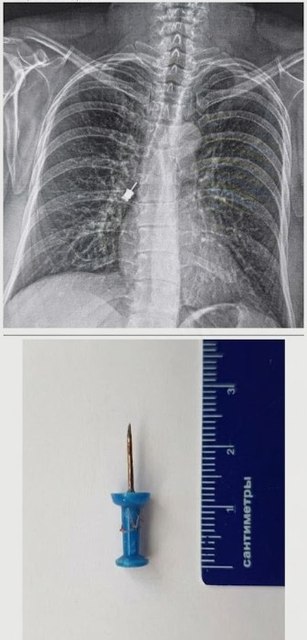

Стоматологічна викрутка: Навіть під час медичних маніпуляцій може статися непередбачуване. Інструмент для імплантації випадково потрапив у дихальні шляхи пацієнта. Лікарі нашого центру успішно впоралися з цим складним завданням.